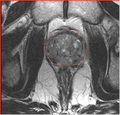

We will evaluate the applicability of the prostate segmentation tools developed by Georgia Tech (Yi Gao) on the 1.5T and 3.0T scans with and without endo-rectal coil.

• evaluate the accuracy of segmentation compared with the manual outlines (we will use the publicly available dataset from MICCAI 2009 Prostate segmentation challenge (1.5T) as well as the images from on-going image-guided biopsy program at BWH (3T T2w, Siemens Magnetom)

• Testing performed using the atlas constructed using MICCAI'09 challenge data (different field strength) for segmenting intra-procedural MRI w/o er-coil obtained at 3T